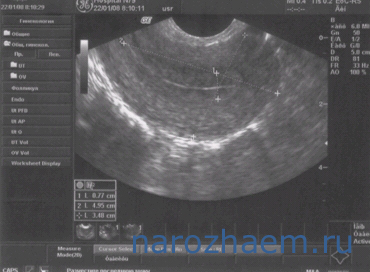

Нормальное изображение яичников.

Как правило, УЗИ яичников выполнить достаточно несложно. Лишь изредка визуализация половых желез может быть затруднена, поэтому врач при помощи датчика ищет ориентир – крупную подвздошную вену.

В протоколе УЗИ указывают несколько размеров яичников: длину (в норме около 30 мм), ширину (в норме не превышает 25 мм) и толщину (у здоровых женщин порядка 15 мм). Суммарный объем яичника не должен быть больше, чем 8 см3. Также следует учитывать, что размеры половых желез могут значительно изменяться в зависимости от дня менструального (физиологического) цикла.

С 8го по 12й день менструального цикла в яичнике начинает образовываться доминантный фолликул, который при проведении УЗИ органов малого таза в этот временной период может быть ошибочно принят за кисту. Если выполнять исследование в день овуляции, то величина фолликула может даже достигать 2,5-3 см.